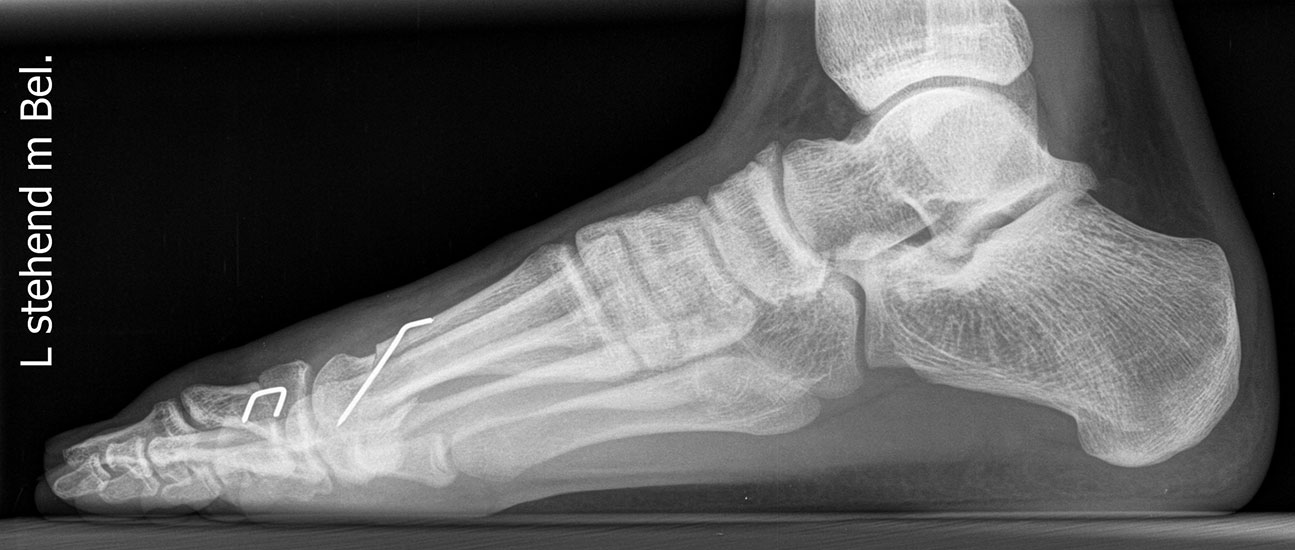

Röntgen

Standard ist die belastete Röntgenaufnahme des Fußes dorso-plantar und seitlich. Günstig ist eine Röhrenkippung von 10°-20°, um die Gelenke der Lisfranc-Linie einsehen zu können.

Ergänzend kann eine Schrägaufnahme hilfreich sein. Bei Metatarsalgien oder Pathologien der Sesambeine liefert die Sprinteraufnahme zusätzliche Informationen. Bei einer Pes planovalgus Fehlstellung wird ergänzend ein Saltzman view durchgeführt.

• Elevation/ Plantarisierung I. Strahl

• Pes metatarsus adductus